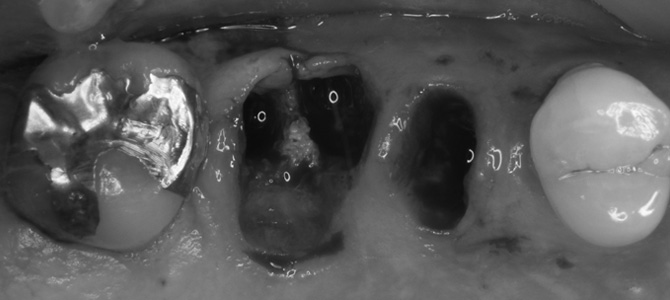

保存不可能な歯を抜歯した後の口腔内写真。

抜歯した直後に、インプラントを埋入した後の口腔内写真。

インプラントと仮歯を連結するための土台を入れた後の口腔内写真。

インプラントを埋入して30分後に仮歯を入れた後の口腔内写真。

インプラントを埋入して3ヶ月後にセラミック歯が入った後の口腔内写真。

(左上の奥から2番目と3番目)